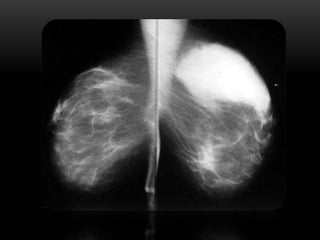

BIRADS 5

• Semiología:

• Nódulo irregular y/o márgenes espiculados, con o sin microcalcificaciones asociadas

• Microcalcificaciones lineales ramificadas

• Recomendaciones y manejo diagnóstico:

• Estudio histológico en todos los casos BAG/BAV

Probabilidad de carcinoma: Mayor de 95%

BIRADS 6

Semiología:

• Categoría asignada a cualquier tipo de lesión en la

que ya exista una confirmación histológica de

malignidad

Recomendación y manejo diagnóstico:

• Estadificación y planificación terapéutica